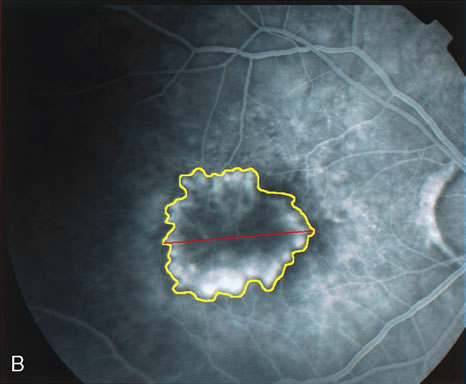

In patients with a shallow neurosensory detachment, the Amsler grid test and visual acuity may be normal. If there is subtle elevation of the neurosensory retina on biomicroscopy examination, FA may demonstrate a CNV before it is symptomatic. It is often easier to evaluate both RPE and neurosensory detachments with good stereoscopic FA pictures than with direct examination.5 Consequently, FA can be helpful in determining the presence and extent of these processes. This is particularly important in patients with CNV due to AMD, because its aggressive course often requires prompt intervention to save central vision.6,7 Furthermore, FA helps in recognizing two types of CNV: classic and occult. Classic CNV consists of a well-defined neovascular membrane, which is apparent in the early phase of the angiogram and shows late leakage of dye beyond its boundaries (Fig. 7 and 8). Occult CNV is seen on by FA as an area of late hyperfluorescence of undefined origin or as a neovascularized PED (Fig. 9 and 10 ). Mixed-type CNV is predominately classic or minimally classic depending on whether the classic component is more or less than 50% of the entire lesion (Fig. 11).

FA is also useful in characterizing two other subgroups of CNV: retinal angiomatous proliferation (RAP)8–16 and polypoidal choroidal vasculopathy (PCV).17–50 RAP begins in the deep retinal complex, forming intraretinal neovascularization (IRN), which may subsequently progress to extend beneath the neurosensory retina, forming subretinal neovascularization (SRN), and a vascularized PED.8 In the later phases of the process there may be a retinal-choroidal anastomosis (RCA). Clinical features of RAP include intraretinal hemorrhages, cystoid macular edema, and associated vascularized PED. FA is useful in revealing the presence of the angiomatous intraretinal vascular complex and the extension of the associated PED (Figs. 12 and 13). However, other diagnostic techniques such as indocyanine green (ICG) angiography, and optical coherence tomography (OCT) may be able to better demonstrate the presence of the RAP lesion.